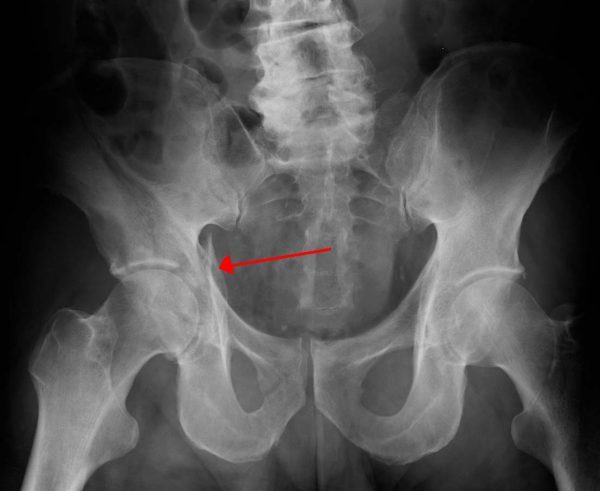

Clinical relevance: pubic ramus fractures

Aetiology - usually low energy falls in the elderly, at standing height.

If isolated, these fractures are treated without surgery.

Healing can be expected in 6-8 weeks. Patients are encouraged to bear weight straight away.

Clinical relevance: pelvic fractures

There are two broad groups of pelvic fractures:

1) Low energy - osteoporotic patients resulting in pubic rami fractures. ‘Stable injuries’ not requiring surgery.

2) High energy - For example RTAs - may include acetabulum and SI joint. These will result in ‘unstable injuries’ and may require surgery. These can associated with soft tissue damage - bladder, urethra, and vascular injury.

Treatment - pelvic binders can be used to stabilise pelvis and minimise bleeding.